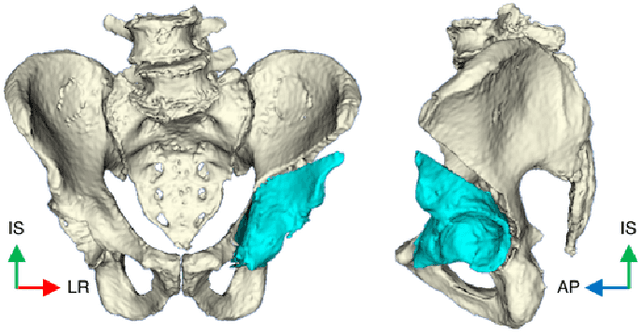

Abstract:Objective: State of the art navigation systems for pelvic osteotomies use optical systems with external fiducials. We propose the use of X-Ray navigation for pose estimation of periacetabular fragments without fiducials. Methods: A 2D/3D registration pipeline was developed to recover fragment pose. This pipeline was tested through an extensive simulation study and 6 cadaveric surgeries. Using osteotomy boundaries in the fluoroscopic images, the preoperative plan is refined to more accurately match the intraoperative shape. Results: In simulation, average fragment pose errors were 1.3{\deg}/1.7 mm when the planned fragment matched the intraoperative fragment, 2.2{\deg}/2.1 mm when the plan was not updated to match the true shape, and 1.9{\deg}/2.0 mm when the fragment shape was intraoperatively estimated. In cadaver experiments, the average pose errors were 2.2{\deg}/2.2 mm, 3.8{\deg}/2.5 mm, and 3.5{\deg}/2.2 mm when registering with the actual fragment shape, a preoperative plan, and an intraoperatively refined plan, respectively. Average errors of the lateral center edge angle were less than 2{\deg} for all fragment shapes in simulation and cadaver experiments. Conclusion: The proposed pipeline is capable of accurately reporting femoral head coverage within a range clinically identified for long-term joint survivability. Significance: Human interpretation of fragment pose is challenging and usually restricted to rotation about a single anatomical axis. The proposed pipeline provides an intraoperative estimate of rigid pose with respect to all anatomical axes, is compatible with minimally invasive incisions, and has no dependence on external fiducials.